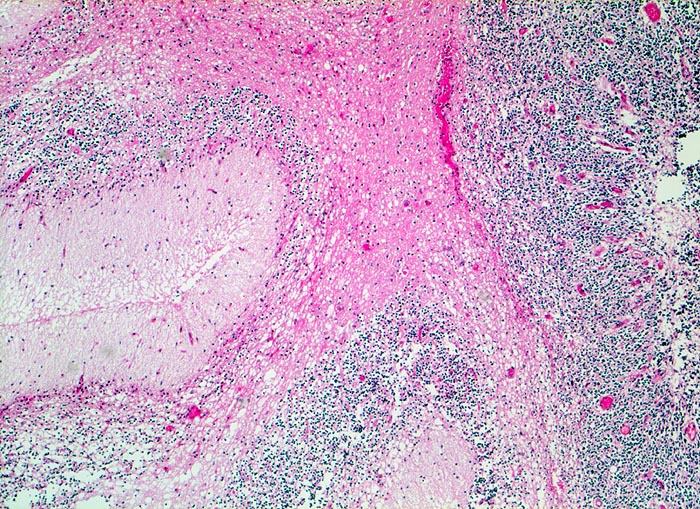

Die Makroskopie ist variabel. Meist sind Medulloblastome unscharf begrenzt, grau und weich, gelegentlich aber auch scharf begrenzt und derb.

Wegen der hohen Zelldichte und der hohen Kern-Zytoplasmarelation erscheinen die Tumoren in der HE Färbung blau. Medulloblastome müssen differentialdiagnostisch von morphologisch ähnlichen kleinzelligen undifferenzierten Karzinomen und Lymphomen abgegrenzt werden. Das klassische Medulloblastom besteht aus dicht gepackten Zellen mit runden bis ovalen oder karottenförmigen stark hyperchromatischen Kernen umgeben von wenig Zytoplasma. Runde Zellen mit weniger dichtem Chromatin sind oft beigemischt. Zahlreiche Mitosen, flächenhafte Nekrosen und Apoptosen sind typisch. In weniger als einem Drittel der Fälle findet man die typischen Homer-Wright Rosetten. Diese bestehen aus ringförmig angeordneten Tumorzellkernen um ein fibrilläres Zentrum aus Zytoplasmafortsätzen.

• Scharf begrenzter rundlicher sehr zellreicher (deshalb blauer) Tumor.